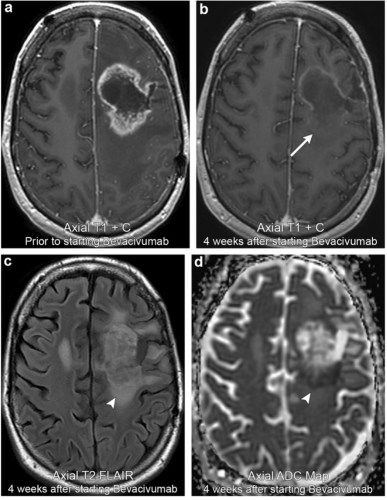

案例2:左额叶星形细胞瘤治疗后MR上呈现假性反应

38岁男性,确诊MR显示左侧额叶病变周围强化。开始贝伐单抗治疗4周后随访MR示增强强化的阶段性减弱(箭头所指)。然而,仍存在持久性T2 FLAIR高信号和表观弥散系数ADC信号减低(箭头所指)。系列后续成像表明T2 FLAIR中的高信号和肿块占位效应属于进展,确认为假性反应。